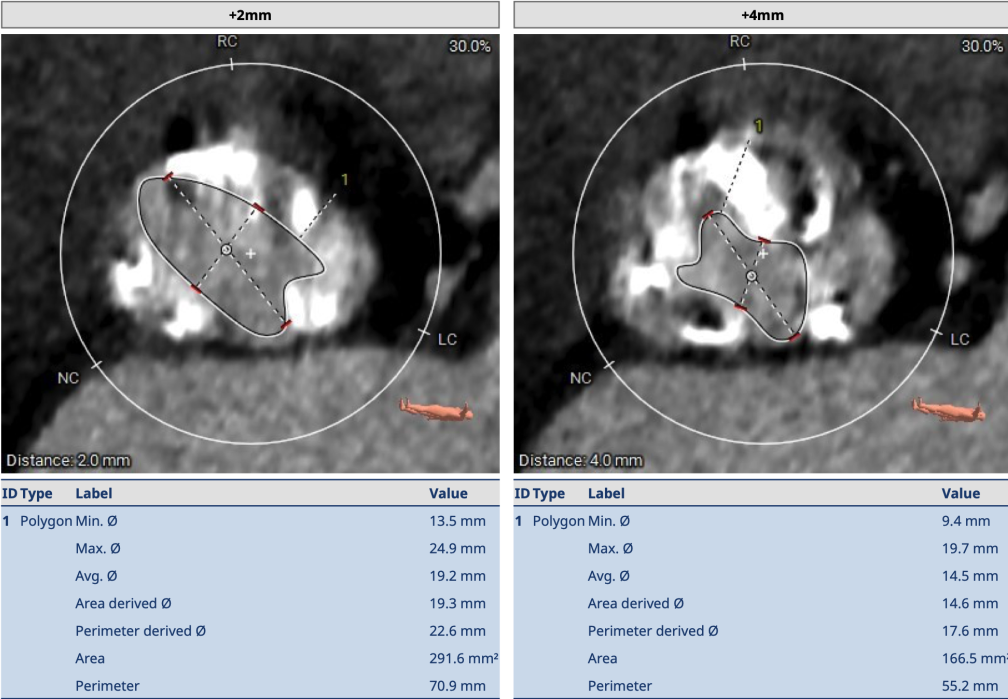

术前CT

术前CT